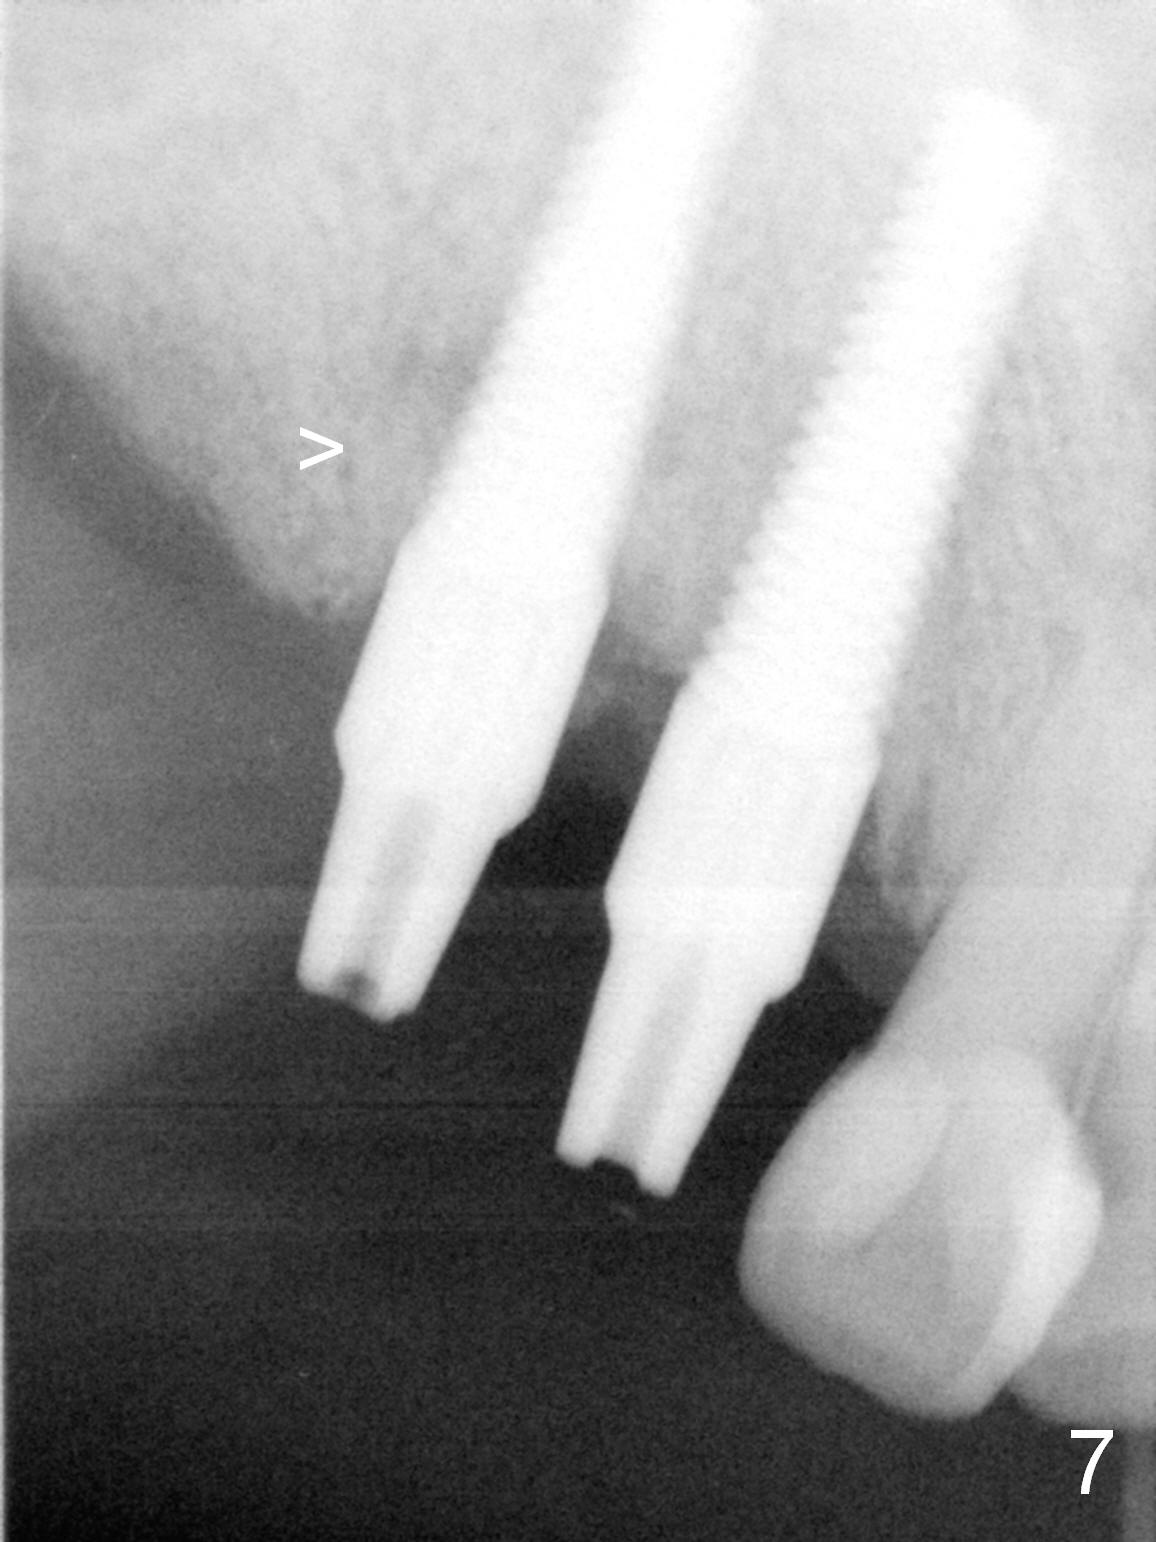

Several of CK's upper teeth (apparently in cross bite) are to be restored with implants (Fig.1). The first two are #5 and 6; note the oval roots (Fig.2). After extraction, and curettage, osteotomy starts in the palatal aspect of each socket. The 1st intraop PA shows that the trajectory at #6 is incorrect (Fig.3). After adjustment, osteotomies look parallel (Fig.4: D: 3.5x20 mm drill; T: 4.5x20 mm tap). This suggests how important it is to use parallel pins to check initial osteotomies for neighboring implants (Fig.3). The trajectory of the implants remains acceptable (Fig.5: 4.5x20 mm with insertion torque »60 Ncm); so is the position of the implants (as palatal as possible; Fig.6 (*: bone graft)). Immediate provisionals are fabricated in cross bite.

Bone density in the distal gap of #5 appears to have increased 3 months postop (Fig.7). Prior to definitive restoration cementation (3.5 months postop), the buccal plate does not collapse (Fig.8). There is no occlusal contact of the new restorations (Fig.9 *), probably due to bite discrepancy (Fig.10,11).